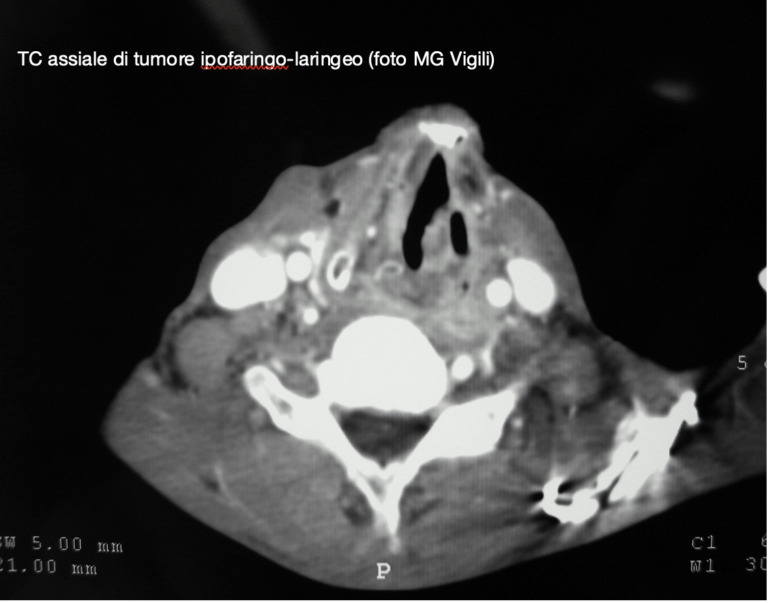

Svuotamento dei linfonodi paratracheali nei tumori ipofaringo-laringei. Quando?